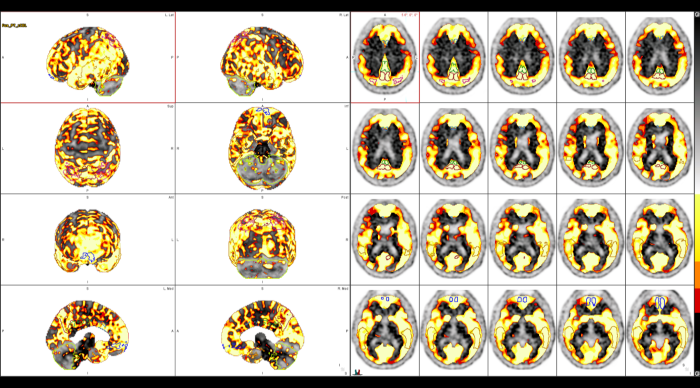

Με τη χρήση ειδικού λογισμικού Τεχνητής Νοημοσύνης (MIM – Lesion ID) πραγματοποιείται αυτόματος υπολογισμός της έκτασης και του όγκου των θέσεων ενεργού νόσου. Ξεπερνώντας τις δυνατότητες του ανθρώπινου οφθαλμού υπολογίζεται το συνολικό φορτίο νόσου πριν και μετά την θεραπεία επιτρέποντας ακριβέστερο χειρισμό του ασθενούς από τον θεράποντα ιατρό.

ΠΟΣΟΤΙΚΗ ΕΚΤΙΜΗΣΗ – ΜΕΤΡΗΣΗ ΟΓΚΟΥ ΝΟΣΟΥ